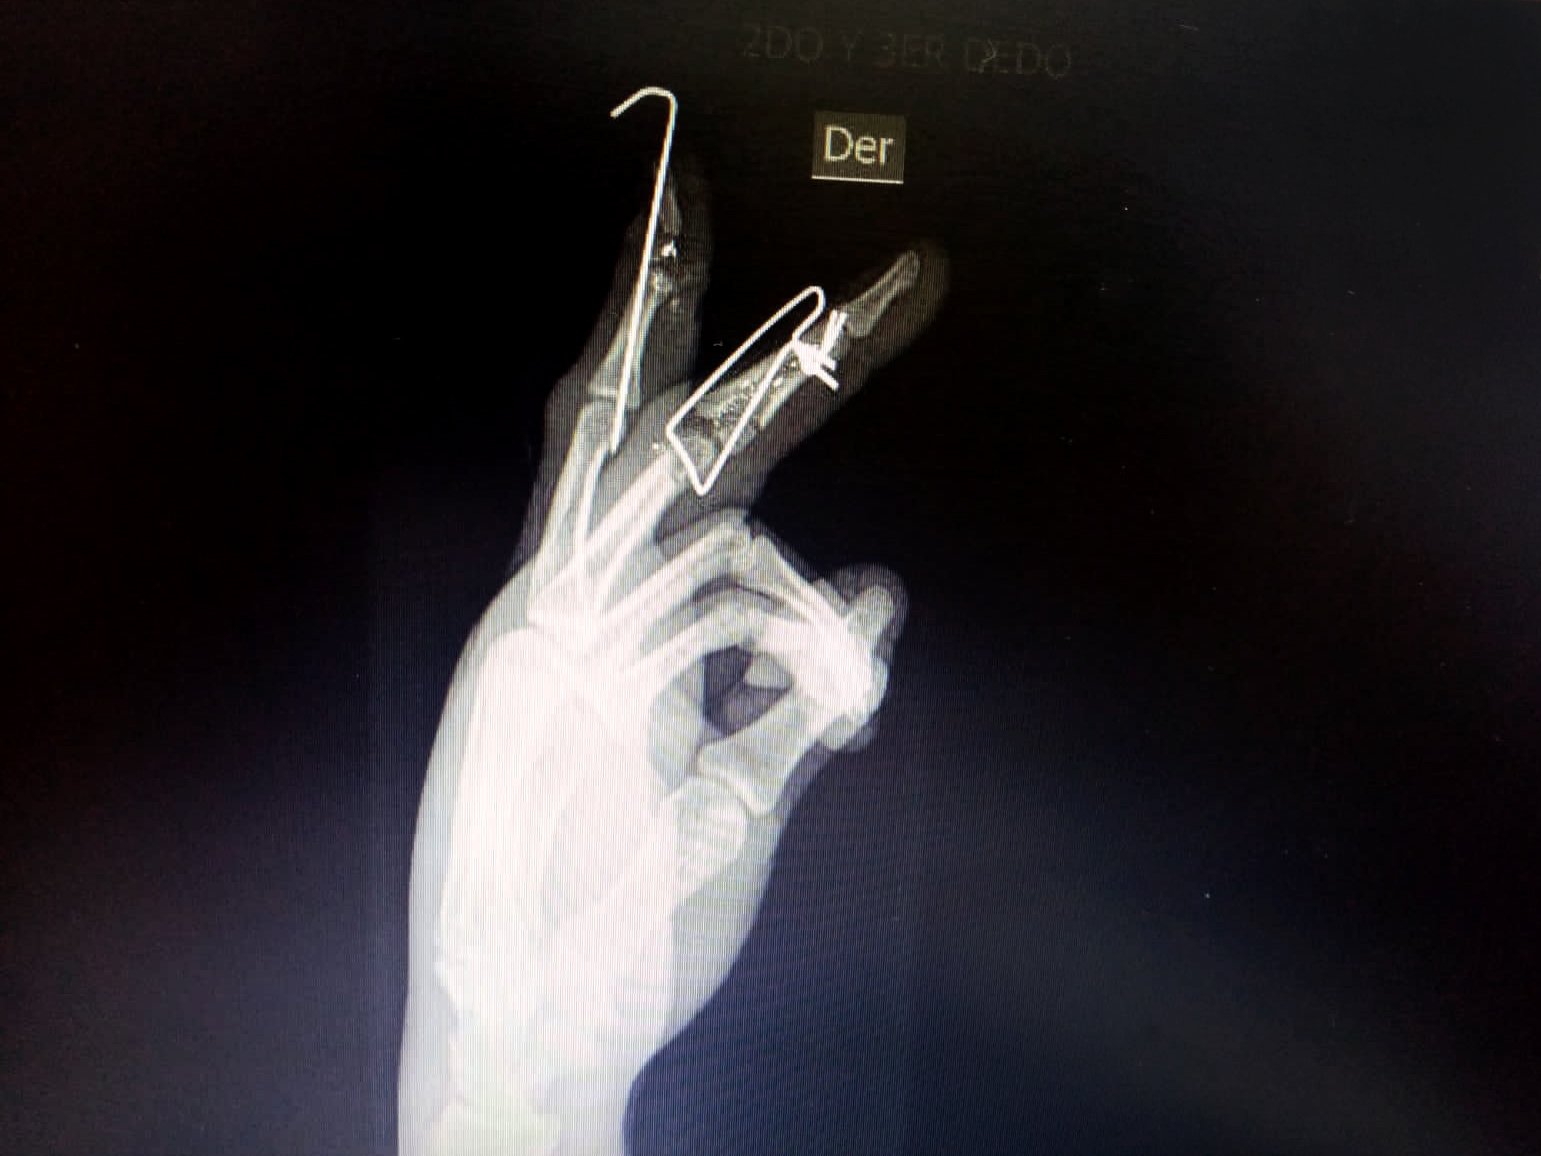

El joven pintor, especialista en acabados de casas y departamentos, buscó el auxilio de una brigada médica voluntaria que le lavó la herida y le hizo un torniquete en la mano con un polo. Pero Bryan sentía que sus dedos latían y el dolor era cada vez más intenso. Supo que tenía que salir de la zona, que ya no podía ayudar en esas condiciones. En los disturbios había perdido contacto con su amigo Jon Cordero, con quien había asistido a la marcha, y no traía su celular para avisarle que debía regresar a su casa en Surquillo. Apenas le contó a su madre de su estado, ambos fueron de emergencia al hospital Casimiro Ulloa, donde conoció la gravedad de sus heridas: varios perdigones le habían fracturado el dedo medio y el dedo índice de la mano derecha. En los exámenes de rayos X pudo ver las fracturas ocasionadas por los proyectiles y cómo varias esquirlas estaban alojadas en sus dedos.

La madrugada del domingo 15 de noviembre no pudo ser sometido a una cirugía por falta de personal en el Casimiro Ulloa. Por eso, tuvo que ir al hospital Dos de Mayo, donde lo operaron para colocarle clavos percutáneos, un procedimiento que implica la inserción de clavos a través de la piel para mantener los huesos en una posición adecuada mientras se consolidan. Bryan Pérez perdió las articulaciones de sus dedos y los médicos le han dicho que será difícil que recupere toda la movilidad.